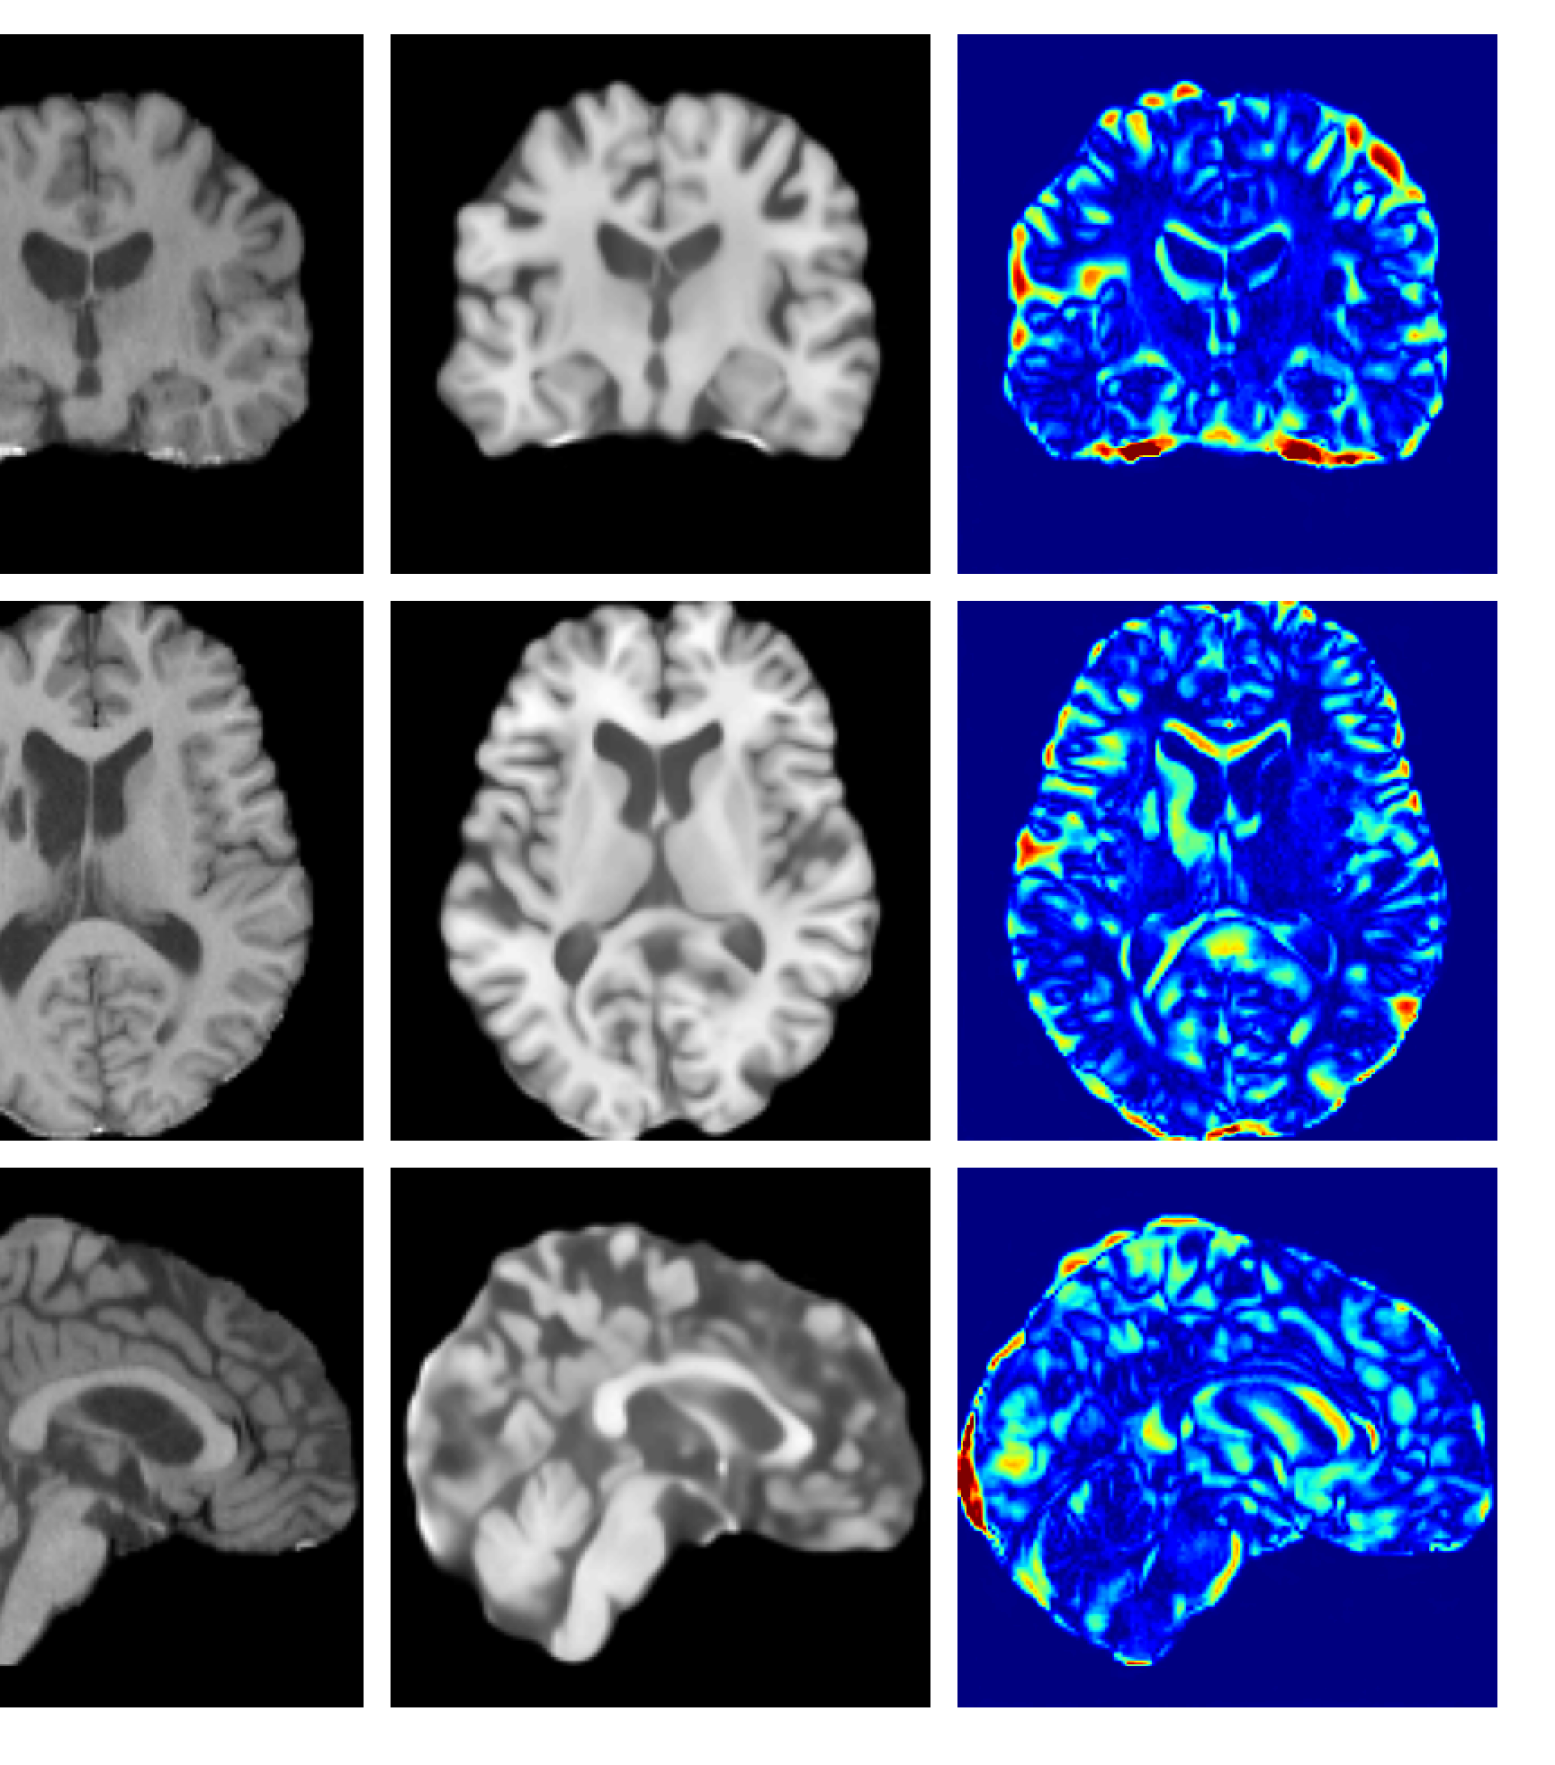

Figure 3: Example reconstructions and anomaly maps for a sample from the disease cohort of the UKBB dataset. Lesion and WMH are indicated in the original image by the red and yellow boxes respectively.

Figures 3 and 4, show example reconstructions and abnormality maps for a sample from the UKBB and UoTH datasets, respectively. Enlarged figures and additional example qualitative results for the ADNI dataset are available in the Supplementary. In Figure 3 we see that whilst all models are able to detect the lesion visible in the sagittal slice, the VAE, cVAE, LDM and LDM (TavgT_{avg}) produce very smooth outputs or lose defining characteristics and thus exhibit more false positives in healthy tissue. THOR and CADD provide the best results, with CADD better detecting white matter hypointensities (WMH). However, neither method fully inpaints all WMH, potentially due to presence of WMH in the healthy training set.

Figure 8: Enlarged example reconstructions and anomaly maps for a sample from the disease cohort of the UKBB dataset. Lesion and WMH are indicated in the original image by the red and yellow boxes respectively.